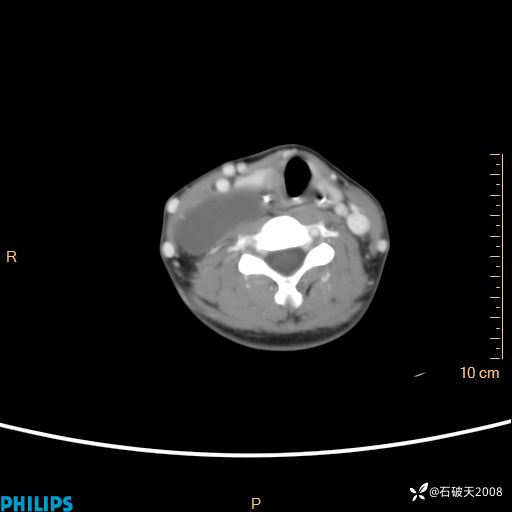

影像诊断要密切结合临床,真的很有必要(病理已公布)

女 21岁 主 诉:发现右侧颈部肿物18年余。

现病史:18年余前患者无明显诱因发现颈部偏右侧有一肿物,具体大小不明确,咳嗽、憋气时肿物增大,局部无疼痛,无吞咽不适,无胸闷及呼吸困难,至当地医院检查考虑良性病变(具体不详)并未做特殊处理,现患者自觉肿物随年龄增长而进一步变大,今日至我院行颈部CT平扫+增强提示:1.右侧颈根部、锁骨上窝及纵隔内异常密度影,考虑良性病变,淋巴管瘤?囊肿?请结合临床。2.双侧颈部小淋巴结。建议结合临床及其他相关检查。现为行进一步治疗,门诊以“颈部局部肿物”为诊断收住我科,发病来患者神志清,精神可,饮食睡眠可,大小便正常,体重无下降。

静脉期